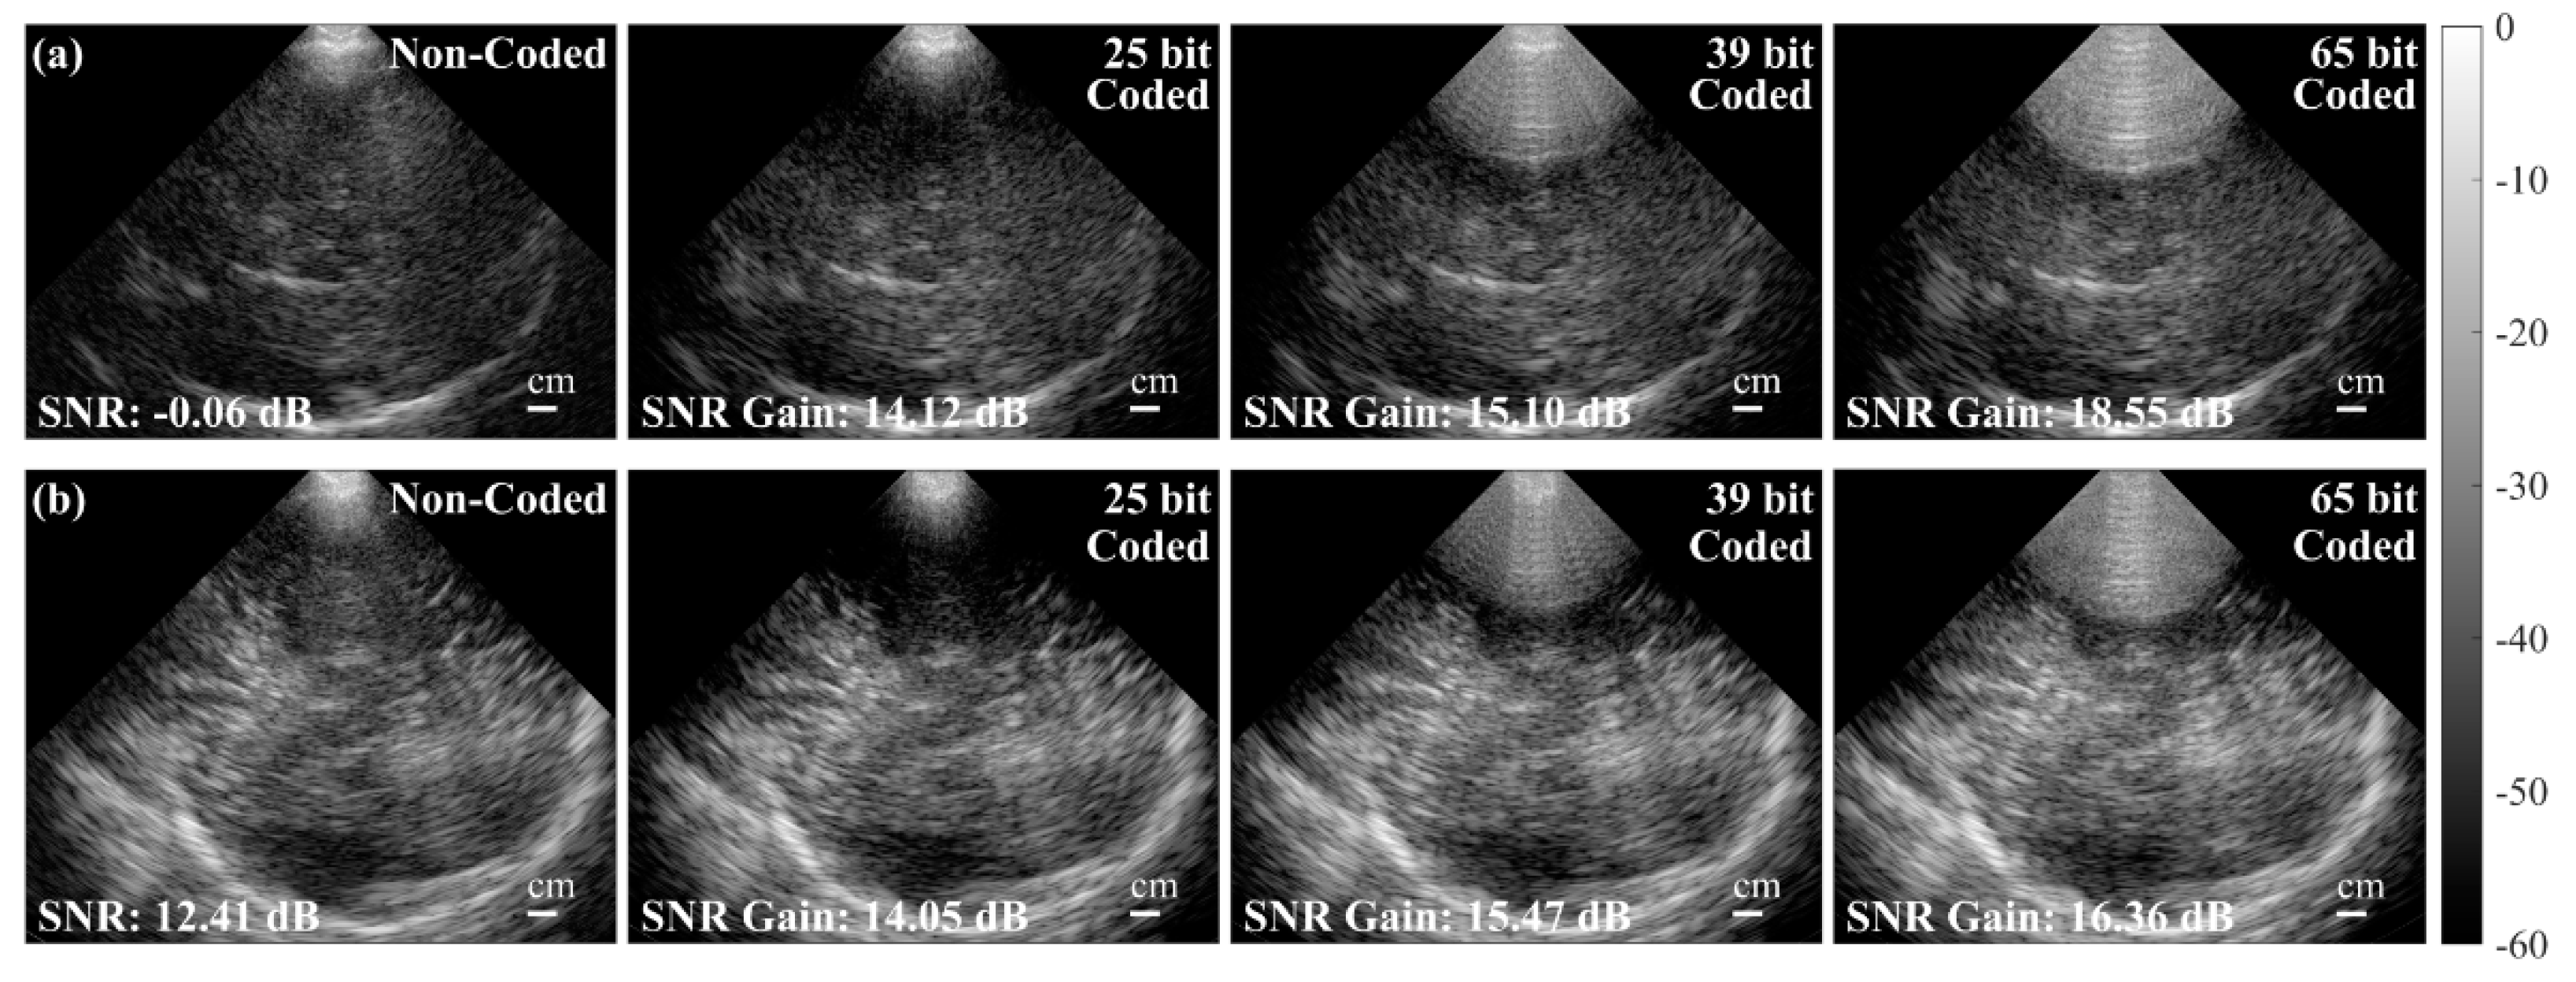

- Vienneau, E.P.; Byram, B.C. A Coded Excitation Framework for High SNR Transcranial Ultrasound Imaging. IEEE Trans. Med. Imaging 2023, 42, 2886–2898. [Google Scholar] [CrossRef] [PubMed]